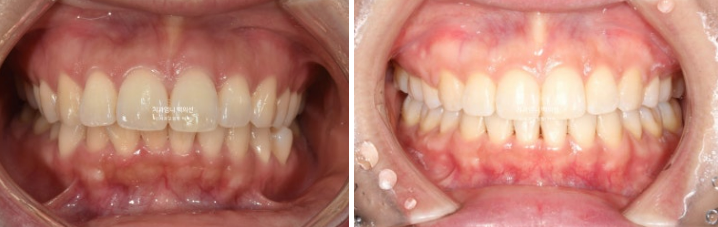

전 후 비교 보겠습니다.

22.09~25.04